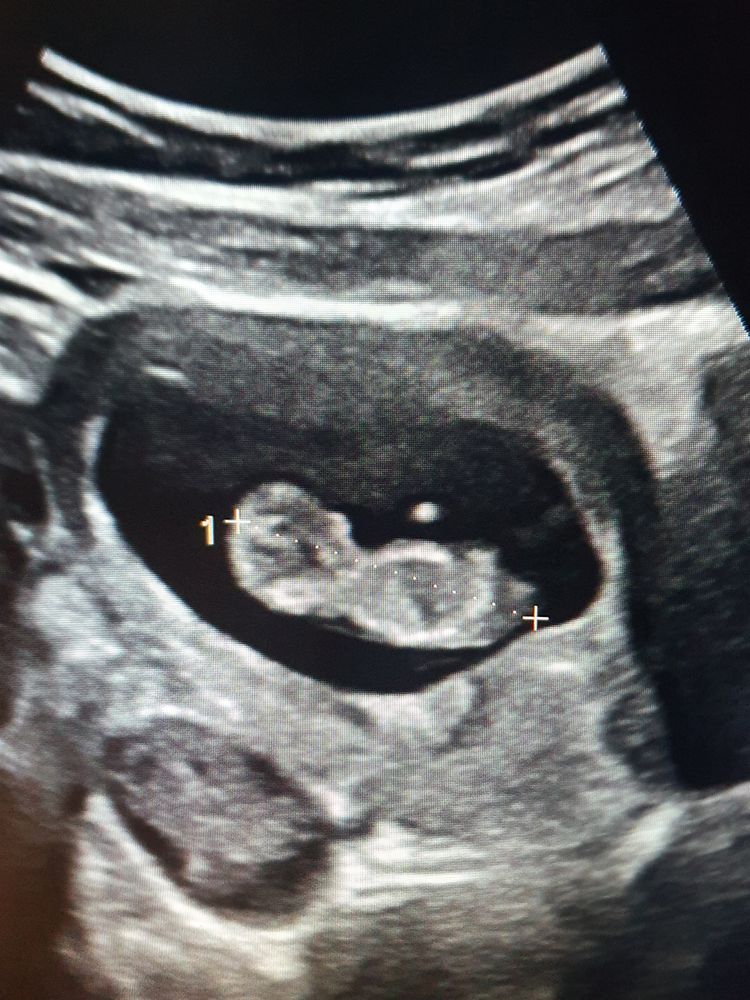

Узи на 10 неделе

Была на узи 10 недели 4 дня ктр 37 мм,когда получила заключение увидела что написано варатниковая зона 2.8 мм ,теперь накручиваю себя и места не нахожу. Кому нибудь измеряли на таком сроке варатниковую зону?